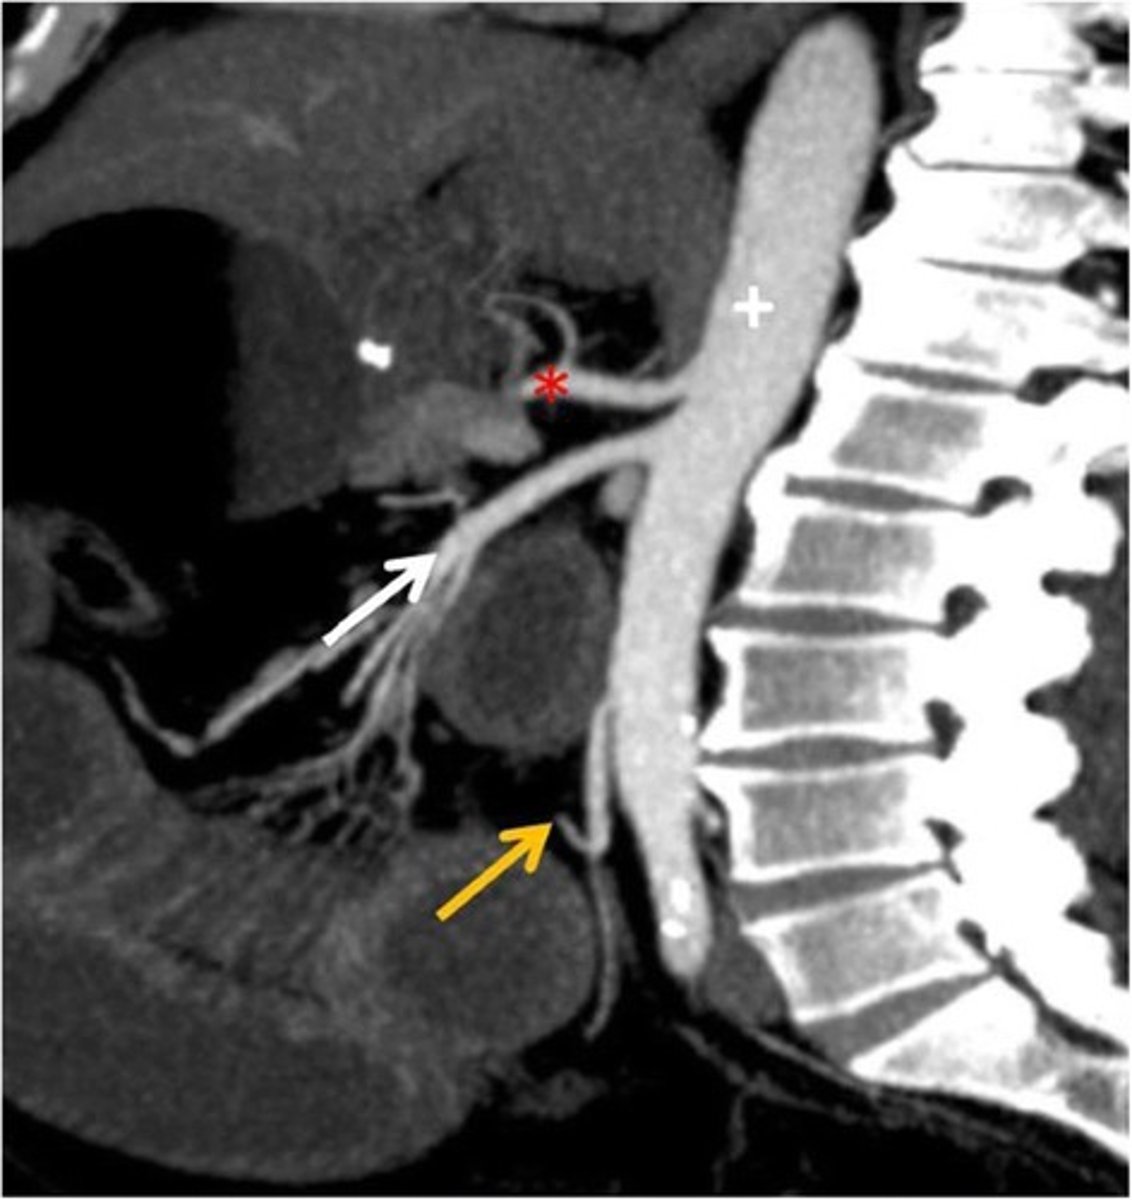

CT Sagittal

What type of image is this

Celiac trunk

What is the red star artery

superior mesenteric artery: midgut

What is the white arrow artery

Inferior mesenteric artery; hindgut

What is the yellow arrow artery